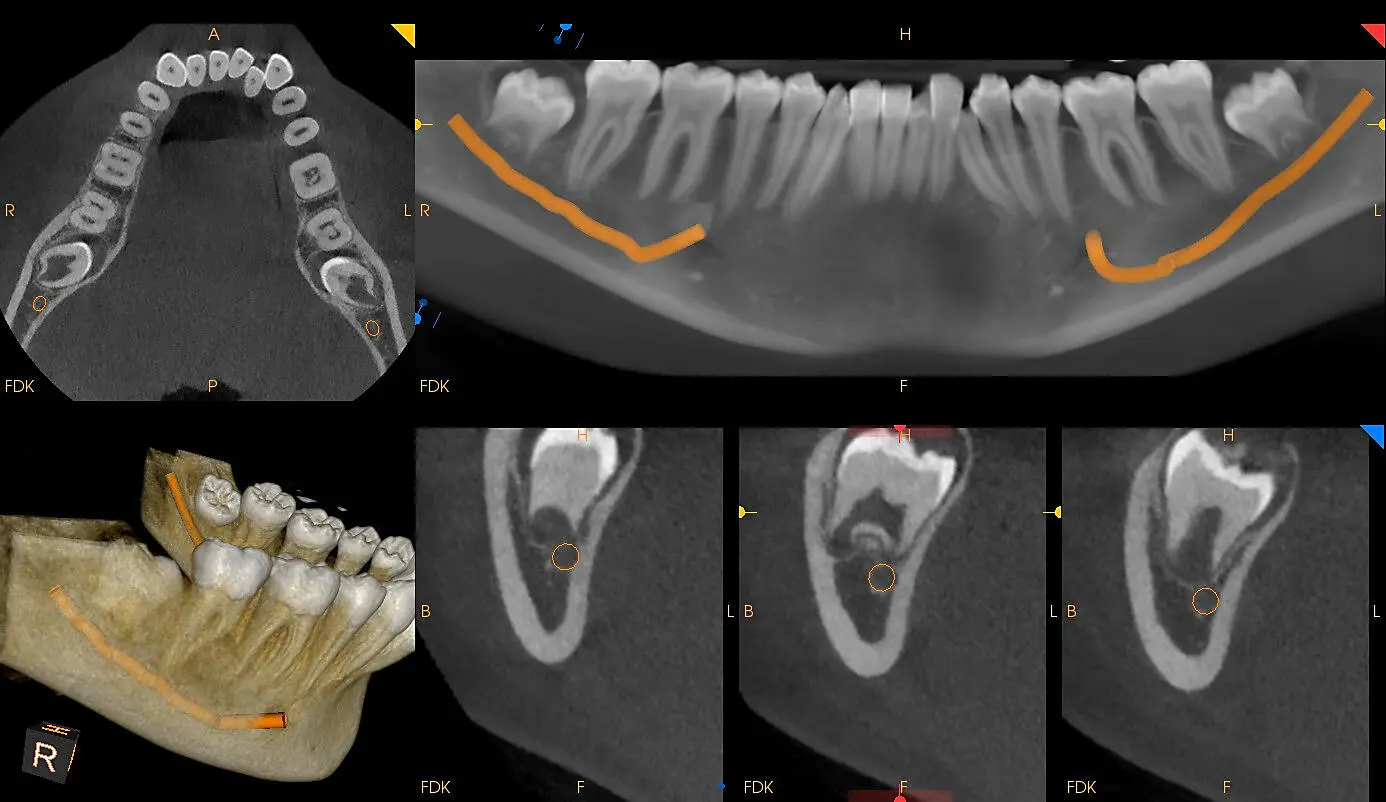

CBCT (Cone Beam Computed Tomography) в Fibo Diagnostic Center — это высокоточное 3D-исследование зубочелюстной системы за один визит.

Мы используем современное оборудование, позволяющее получать детализированные снимки с минимальной лучевой нагрузкой. CBCT даёт полное представление о состоянии зубов, костных структур, корней и суставов.

3D-снимок одной или обеих челюстей в высоком разрешении.

Файлы в формате, совместимом с любым CAD/CAM ПО.

Вы получите интерактивный 3D-снимок, на котором чётко видны: зубы и корни, костные структуры челюсти, гайморовы пазухи, суставы ВНЧС.

Файл можно просматривать в специализированных программах или передать вашему врачу/лаборатории для планирования лечения.

Как выглядит результат?

Фотореалистичная 3D-модель лица

Возможность виртуальной примерки будущих конструкций;

Возможность рассматривать результат под любым углом.